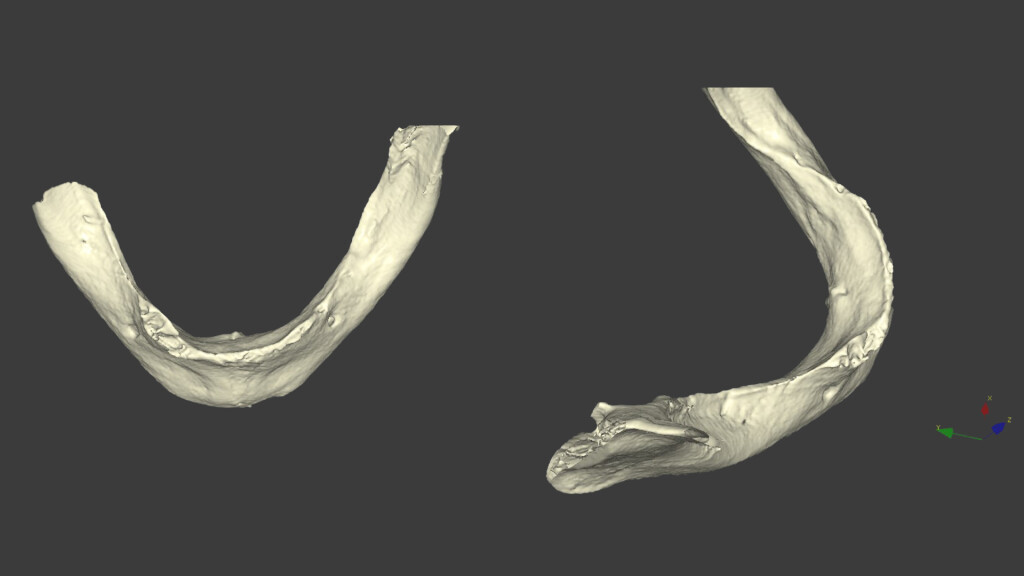

Per essere il più efficace possibile, ho pensato di stampare la CBCT ed eseguire sul modello l’intervento di All-on-4, facendo alcune considerazioni sull’osteotomia e sul posizionamento degli impianti.

Questa è la situazione del paziente: